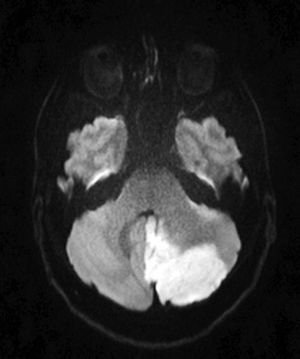

This cerebellar infarction is most likely to be caused by: A)Cervical left vertebral artery dissection B)Thrombus in the basilar artery C)Extrinsic compression of the left vertebral artery D)Calcified atherosclerotic occlusion of the left vertebral artery